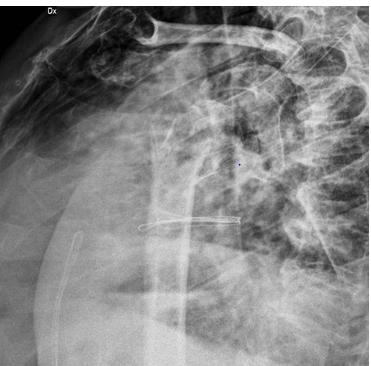

Radiographic checks showed a partial loss of reduction and physio-kinesitherapy was indicated but she was unable to underwent to treatment because of the new social restrictions. Further radiographs showed gradual loss of reduction. Therefore, we started contemplating a definitive treatment by performing a ORIF with bone graft or a shoulder arthroplasty, but at that moment, the patient was lost at follow-up. Given the poor bone quality, after the removal of the EF, we would probably have implanted a hemiarthroplasty or a reverse prosthesis with a press-fit primary humeral stem fixation, considered an optimal choice because of the possible easier revision, decreased operative time, healing time, and resolution of the symptoms [16]. After 7 months, the patient came back to our department, suffering from pain and severe functional limitation, compounded by a preternatural movement of the joint. Radiographs showed evident dislocated nonunion with reabsorption of tuberosities and metaphysis.

Therefore, our choice has been to implant a reverse shoulder prosthesis with a cemented trauma stem “Equinoxe” by Exactech number 8 mm. This choice involved several compromises like technical difficulties due to the severe bone loss and higher risks of dislocations, infections, nerve injuries and thromboembolism due to the use of cement, compared to an arthroplasty with a pressfit stem [17-20]. At three-month follow-up, the patient showed no pain and a sufficient function of the joint. Since the exact amount of loss to follow-up is not valuable, there is a chance that cases of nonunion in longstanding fractures like this could increase in the near future. Our experience shows that cemented stem fixation can be an important choice of treatment for these patients. Other strategies, like telemedicine, should be considered and eventually implemented to prevent this kind of consequences resulting from the pandemic [21-23].